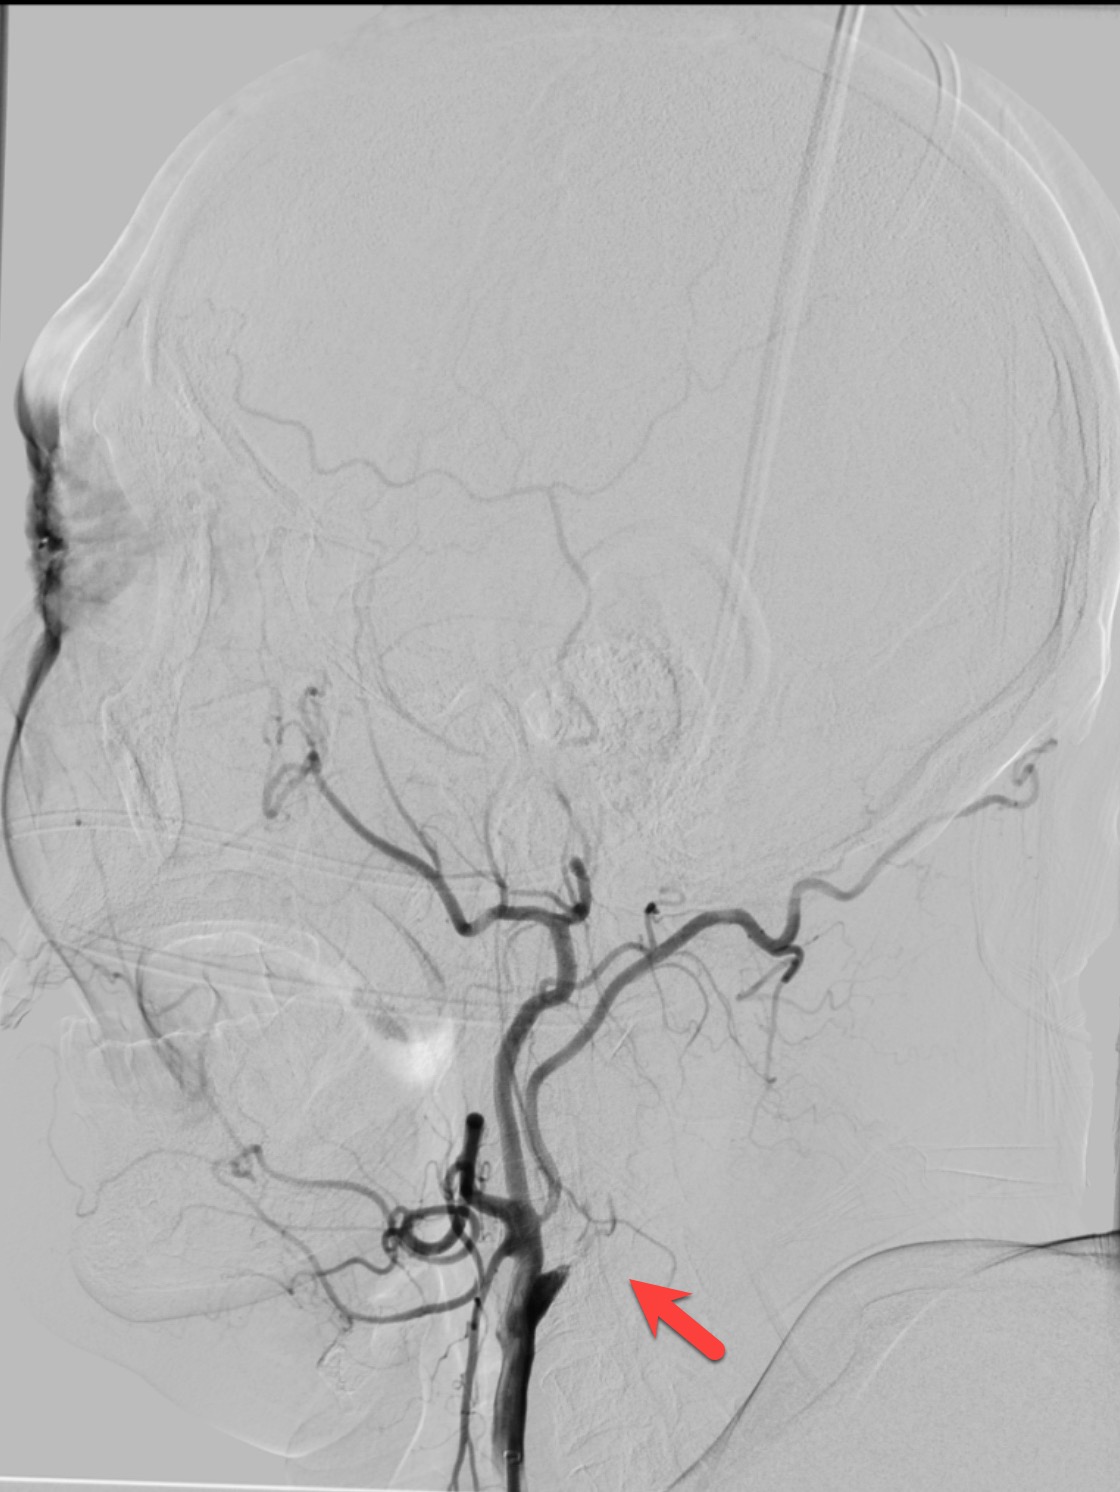

右侧颈内动脉及大脑中动脉恢复通畅

血管介入科医生凭借精湛的技术和丰富的经验,成功地完成了通过颈内动脉闭塞段、颈内动脉血栓抽吸、大脑中动脉取栓支架就位、取出大脑中动脉血栓、植入颈内动脉支架等一系列操作,成功地开通了血管,恢复了颅内的血流。经过血管介入科医生及护士的细心照顾,患者最终恢复了健康,没有残留明显的明显的后遗症。